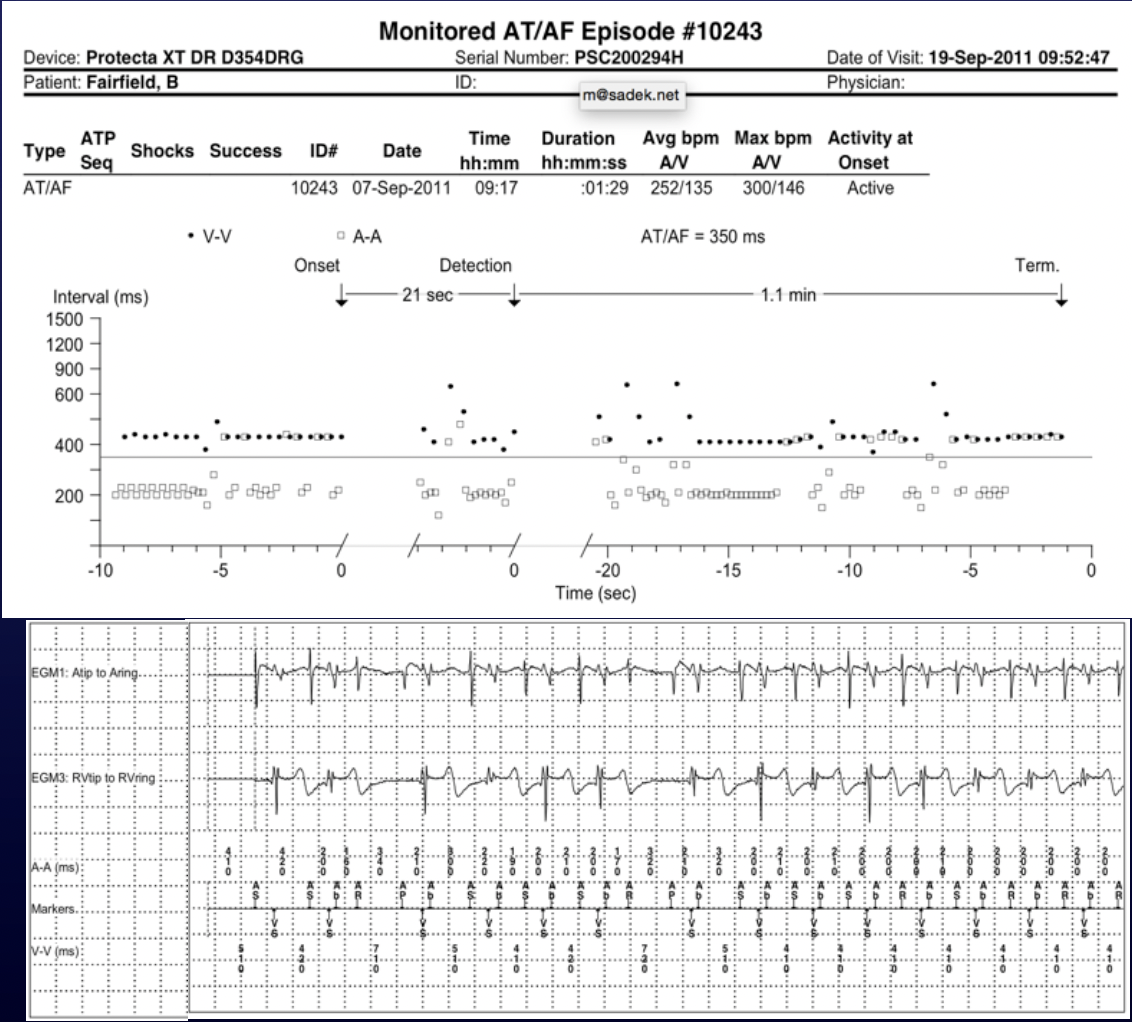

Diagnosis?

Atrial Fibrillation with RVR